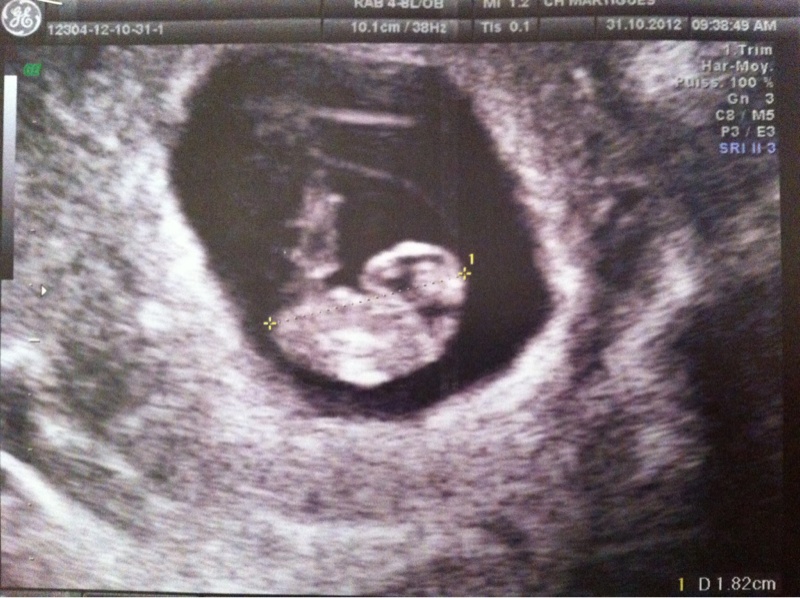

en ce qui me concerne aujourd'hui 1er rdv gygy, donc mini écho lol, j'ai pu entendre son p'tit coeur, et dpa pour le 17juin, à fixer à l'écho du 28/11, voilà c'était un beau cadeau d'anniversaire...